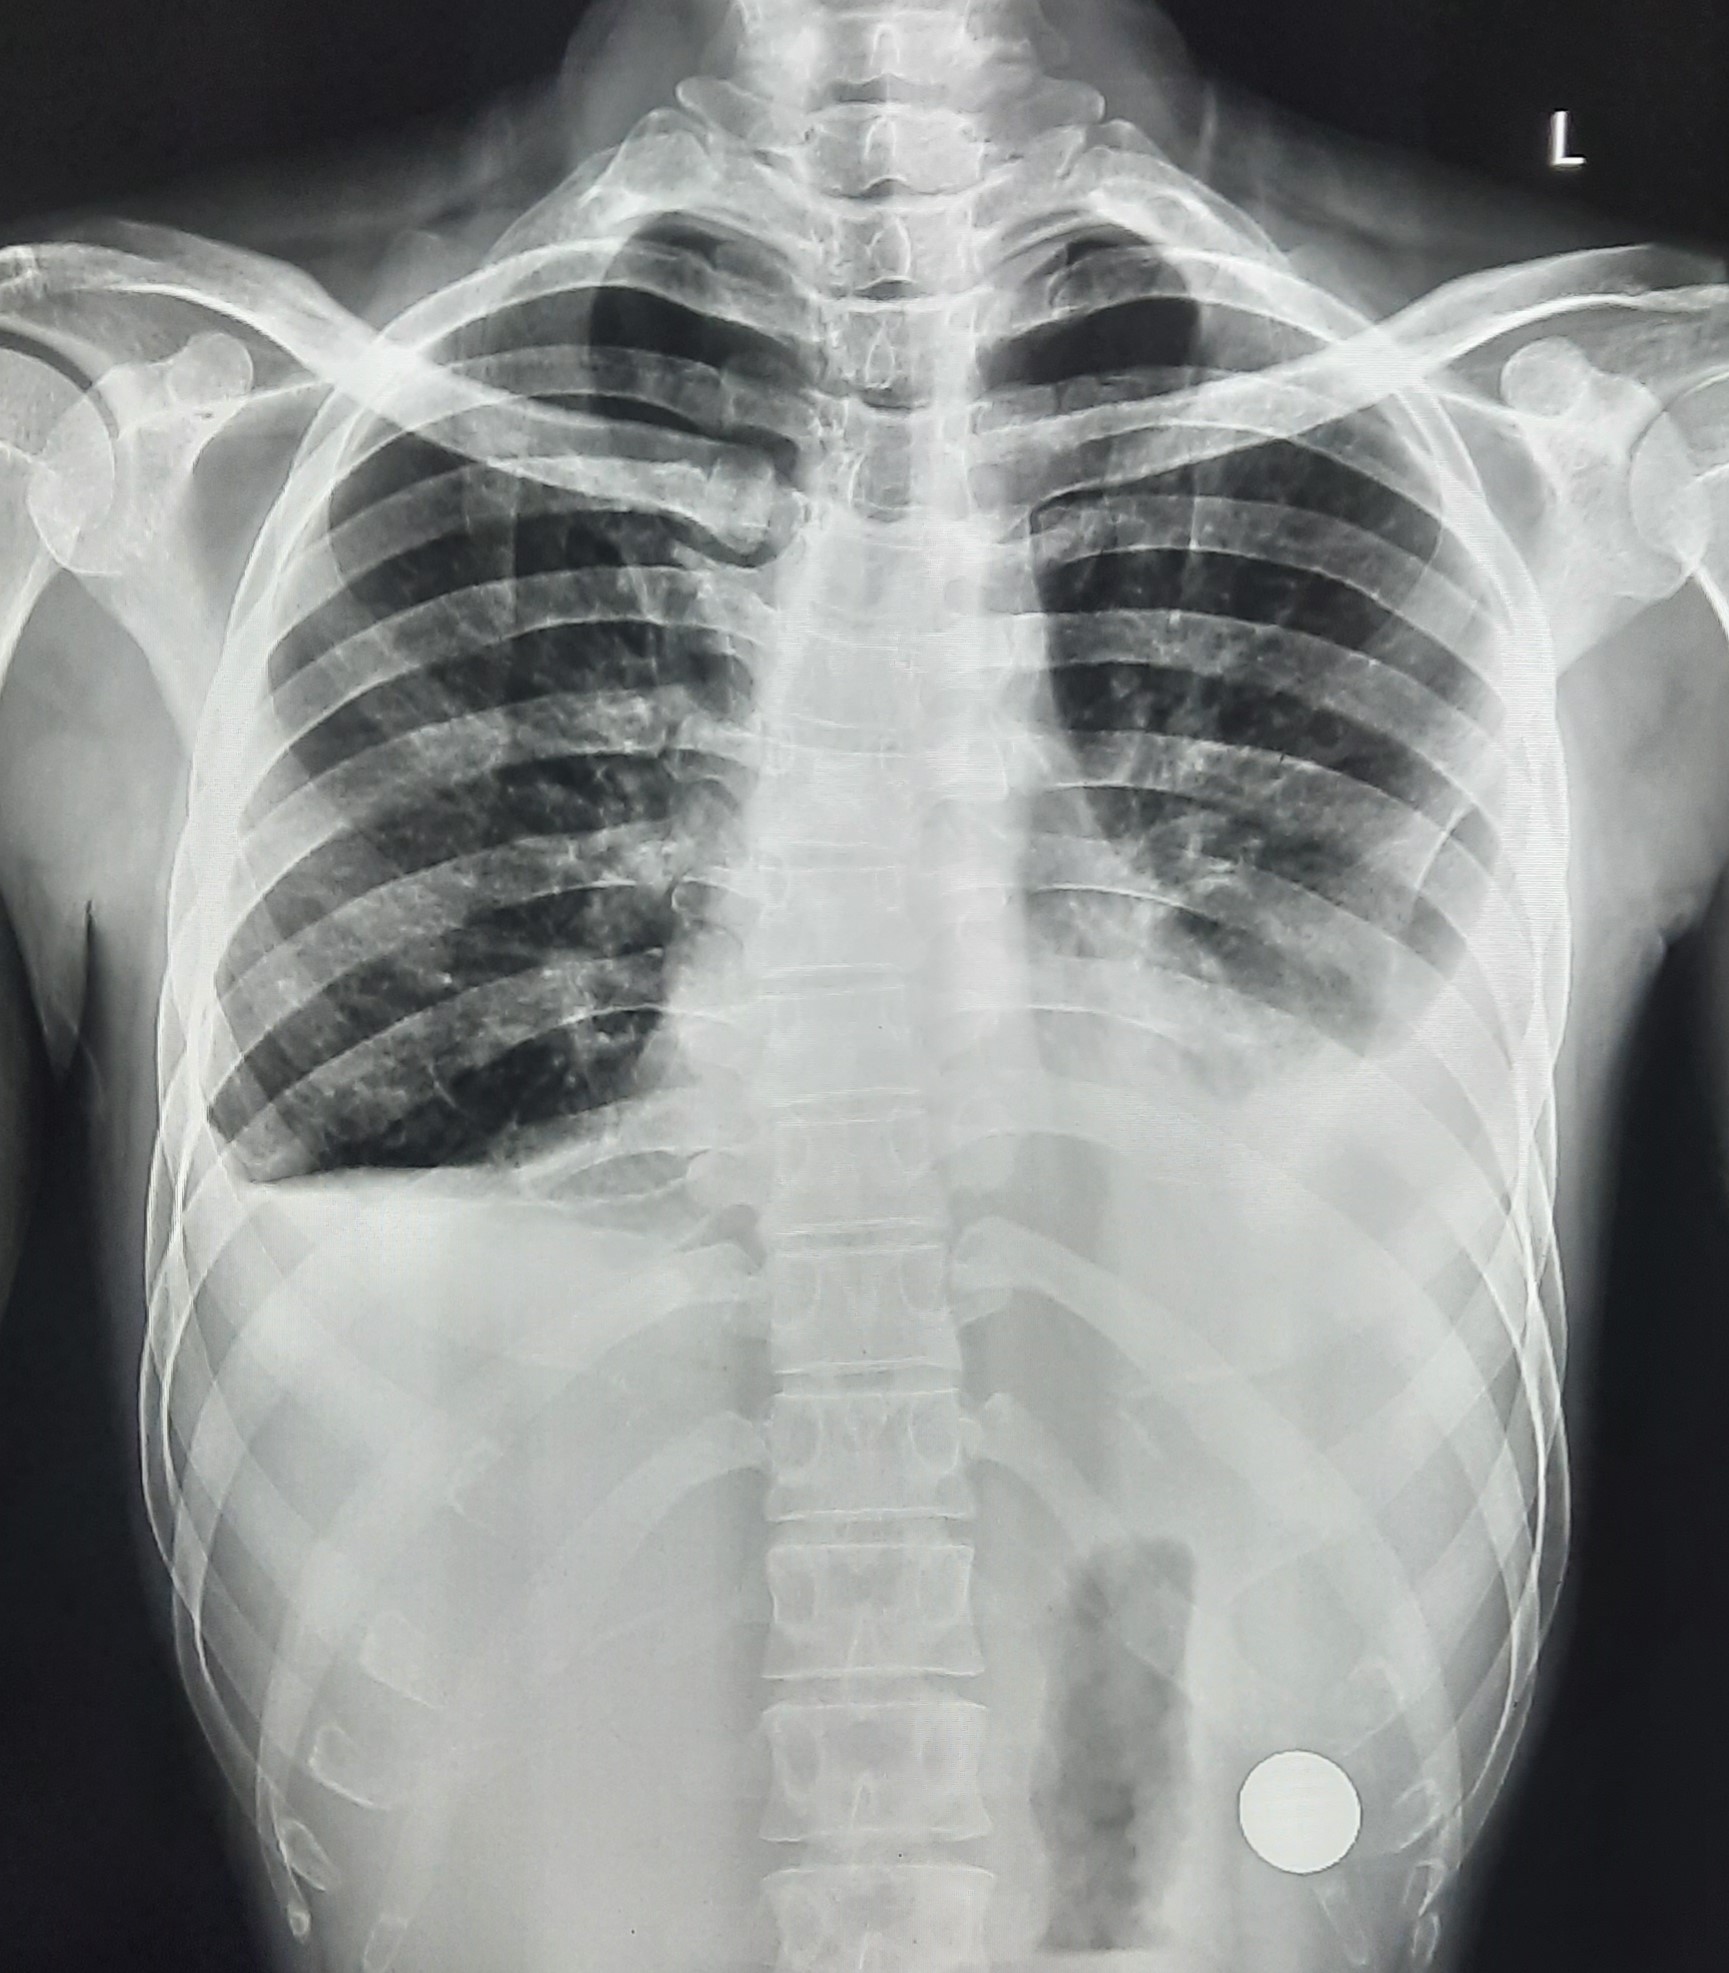

| 102 | IGGMC, Nagpur, Nagpur | P2 | 29-4370 | Prachi Bawane | Consent taken on Paper | 17 Yrs. |

Provisional Diag : PTB?

Final Diag : Active Pulmonary Tuberculosis With Tuberculi? Right Sided Pleural Effusion |

TB Case (Confirmed) | Bilateral ill Defined, No Homogenous Reticulonodular opacities, Right CP Angle Blunting | Abnormality visible on x-ray |